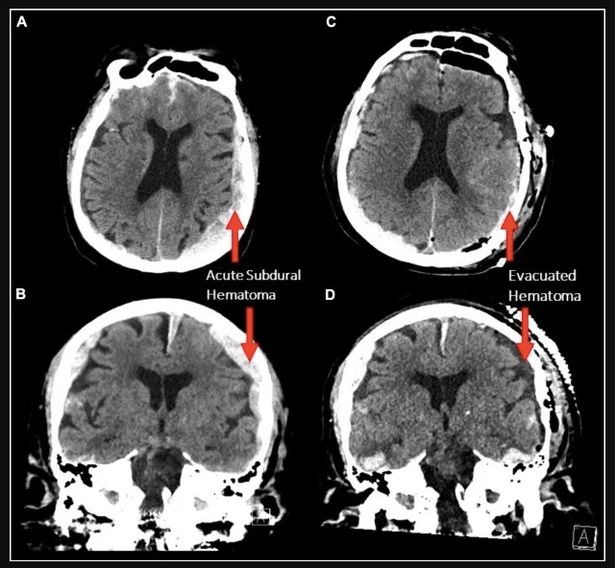

ومع ذلك، بالرغم من الافادات الكثيرة التي حُصِّلت على مدى مئات السنين من الذين جرى إنعاشهم بعد الموت السريري أو كادوا أن يفارقوا الحياة، ”لقد صُدمت عندما أدركت أننا لا نعرف شيئًا تقريبًا“ عن نشاط الدماغ أثناء الاحتضار، كما تقول بورجيغين. بالنسبة للدراسة الراهنة، درست هي وفريقها السجلات الطبية لأربعة أشخاص كانوا في حالة غيبوبة وعلى أجهزة الانعاش [أجهزة تستخدم لإبقاء المريض على قيد الحياة [5] ] الذين وضع الأطباء عليهم خوذات تخطيط كهربية الدماغ. لم يكن من المتوقع أن يبقى أي من هؤلاء المرضى على قيد الحياة.

الخوذات ترصد باستمرار الإشارات الكهربائية التي تنشط عبر القشرة المخية [6] cerebral cortex لكل مريض: قبل وبعد إزالة الأطباء أجهزة التنفس الصناعي، وأثناء آخر نبضة قلب قابلة للقياس لكل مريض، وحتى تَوقَف نشاط الدماغ بشكل تام. بعد ثوانٍ من إزالة أجهزة التنفس الصناعي، اجتاحت دماغي اثنين من المرضى الأربعة فجأة موجات من النشاط العصبي عالية التردد تسمى موجات غاما gamma, والتي استمرت مع توقف القلب عن النبض. وجدت دراسات أخرى [7] نفس النمط من نشاط موجات غاما عندما يكون شخص سليم منهمكًا في التذكر أو التعلم أو حين يحلم، وقد قرن بعض علماء الأعصاب هذه الموجات بالوعي.